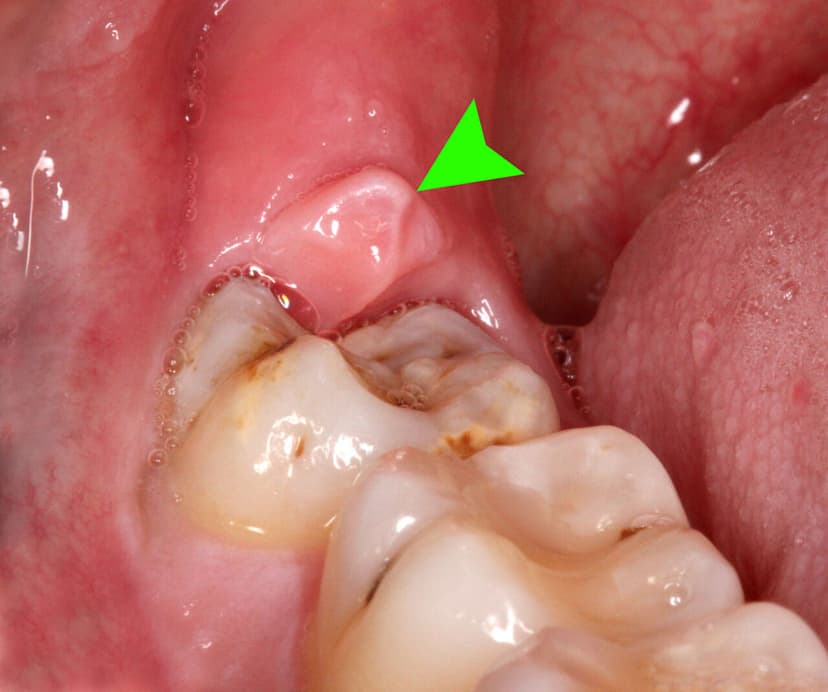

Lợi trùm là tình trạng nướu (lợi) mọc phủ lên một phần của răng, thường gặp nhất là răng khôn (răng số 8), khiến thức ăn, vi khuẩn dễ tích tụ, gây viêm nhiễm và đau nhức.

Lợi bị trùm có thể xuất hiện ở một hoặc cả hai bên hàm, phổ biến nhất là vùng hàm dưới. Ở mức độ nhẹ, người bệnh chỉ cảm thấy cộm, khó chịu khi nhai. Nhưng nếu không được điều trị sớm, vùng lợi này có thể sưng to, đỏ, thậm chí mưng mủ gây viêm lợi bị trùm nặng.